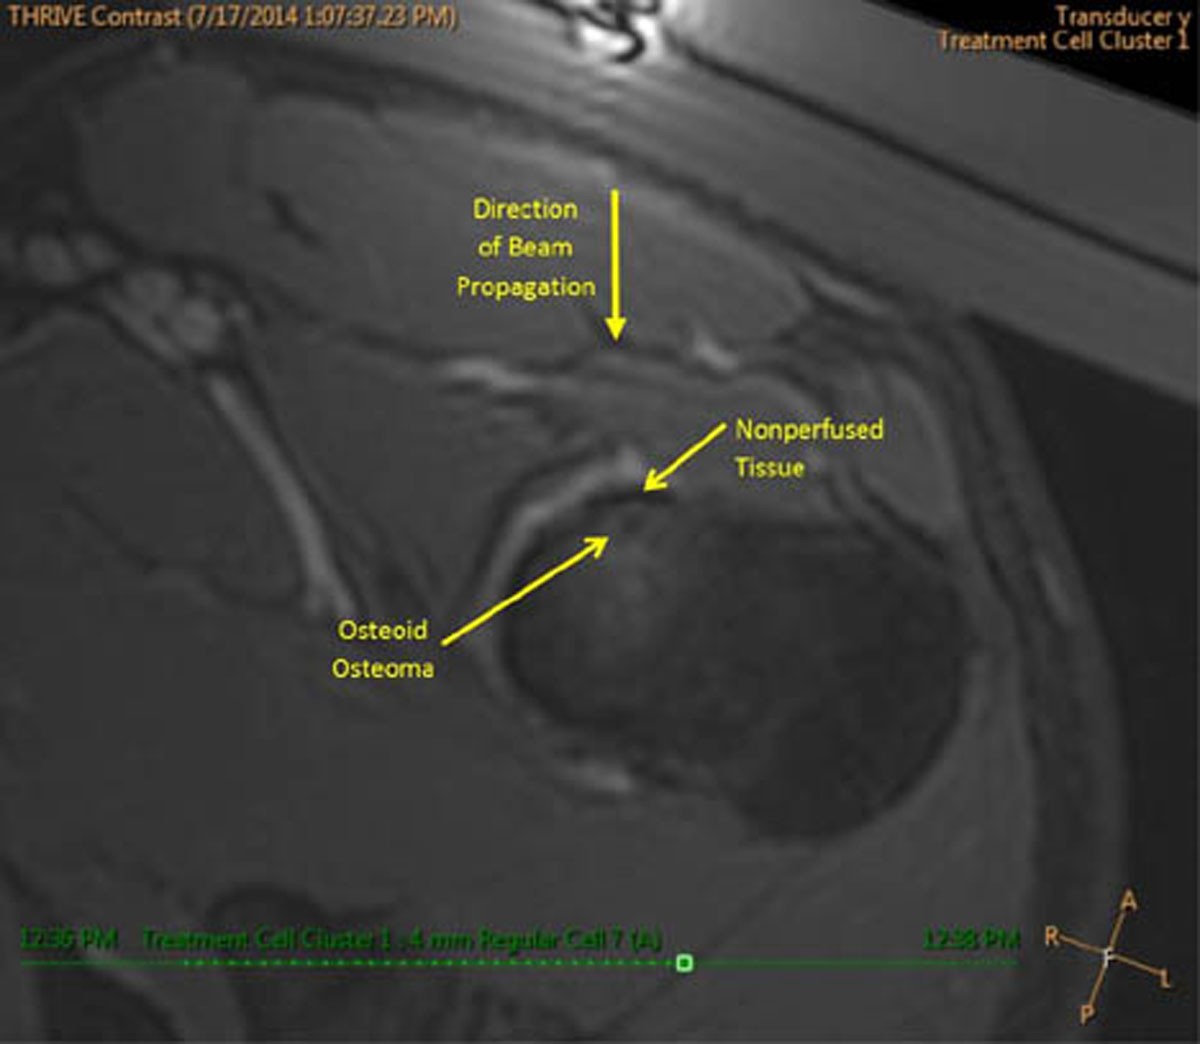

Figure 3

Gadolinium enhanced T1-w image of the osteoid osteoma and treatment area following thermal ablation. A small region of non-perfused tissue is visible at the bone surface, adjacent to the osteoid osteoma lesion that is approximately the same extent as the thermal dose contour.